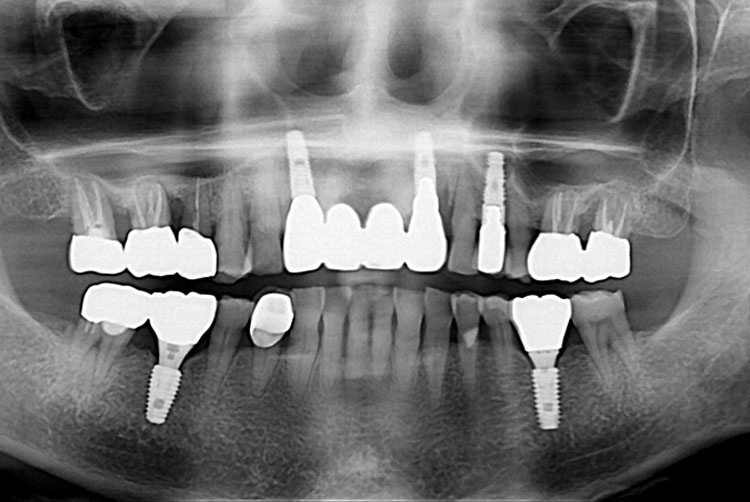

[임플란트] 임플란트

치료후 : 2018-09-27

세종치과는 많은 환자와 다양한 케이스를 바탕으로 항상 편안한 임플란트 수술을 제공하고자 노력하고,

오래동안 튼튼히 쓸 수 있는 임플란트 수술을 가장 큰 목표로 삼고 있습니다.